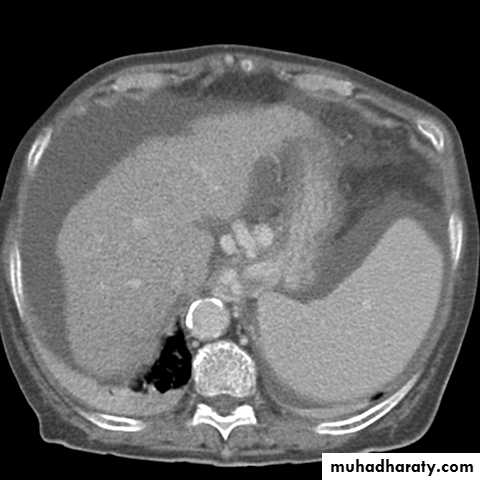

CT scan

Cirrhosis & portal hypertension